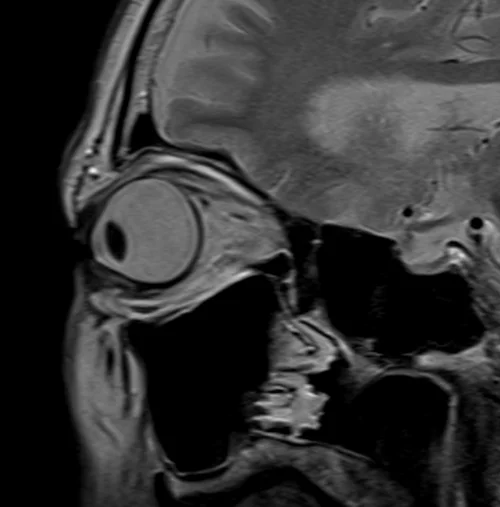

MRI Orbits T2 sagittal oblique images